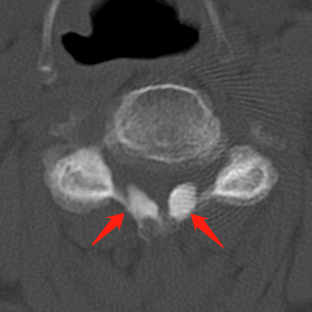

术前MRI影像提示胸椎黄韧带肥厚,胸段脊髓信号改变。

术前术后CT影像资料